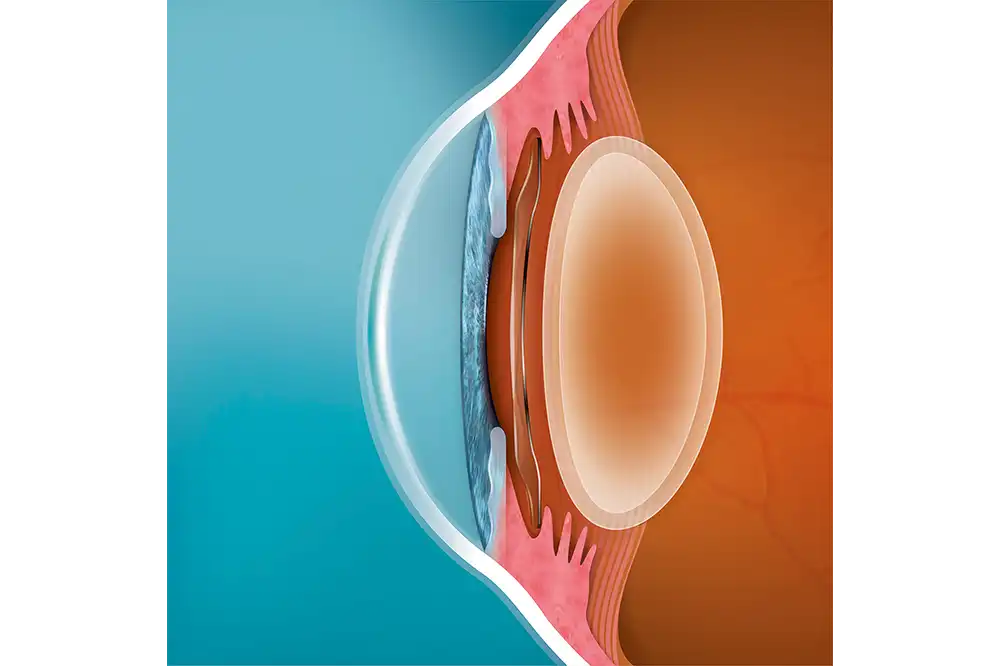

- EVO ICL is een phake lens.

- EVO wordt direct achter de iris en vóór de natuurlijke kristallijne lens geplaatst.

- De EVO ICL-procedure vereist geen verwijdering van corneaweefsel.

- De EVO-lens is een reversibel implantaat.

- Behoudt zowel cornea als natuurlijke lens3